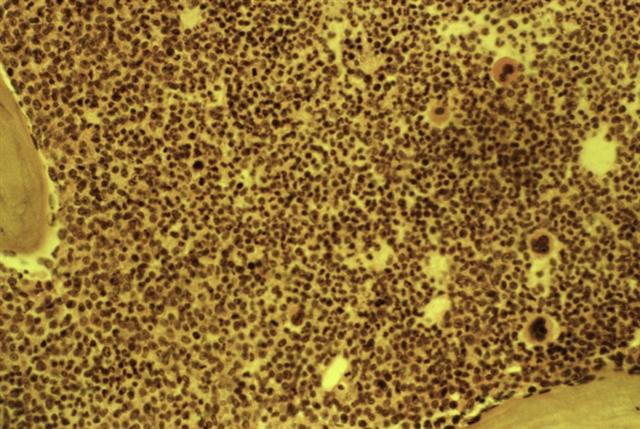

Рис. 6. Рентгенограмма бедренной кости при остром лейкозе (прямая проекция): продольно-разволокненная структура костного вещества.